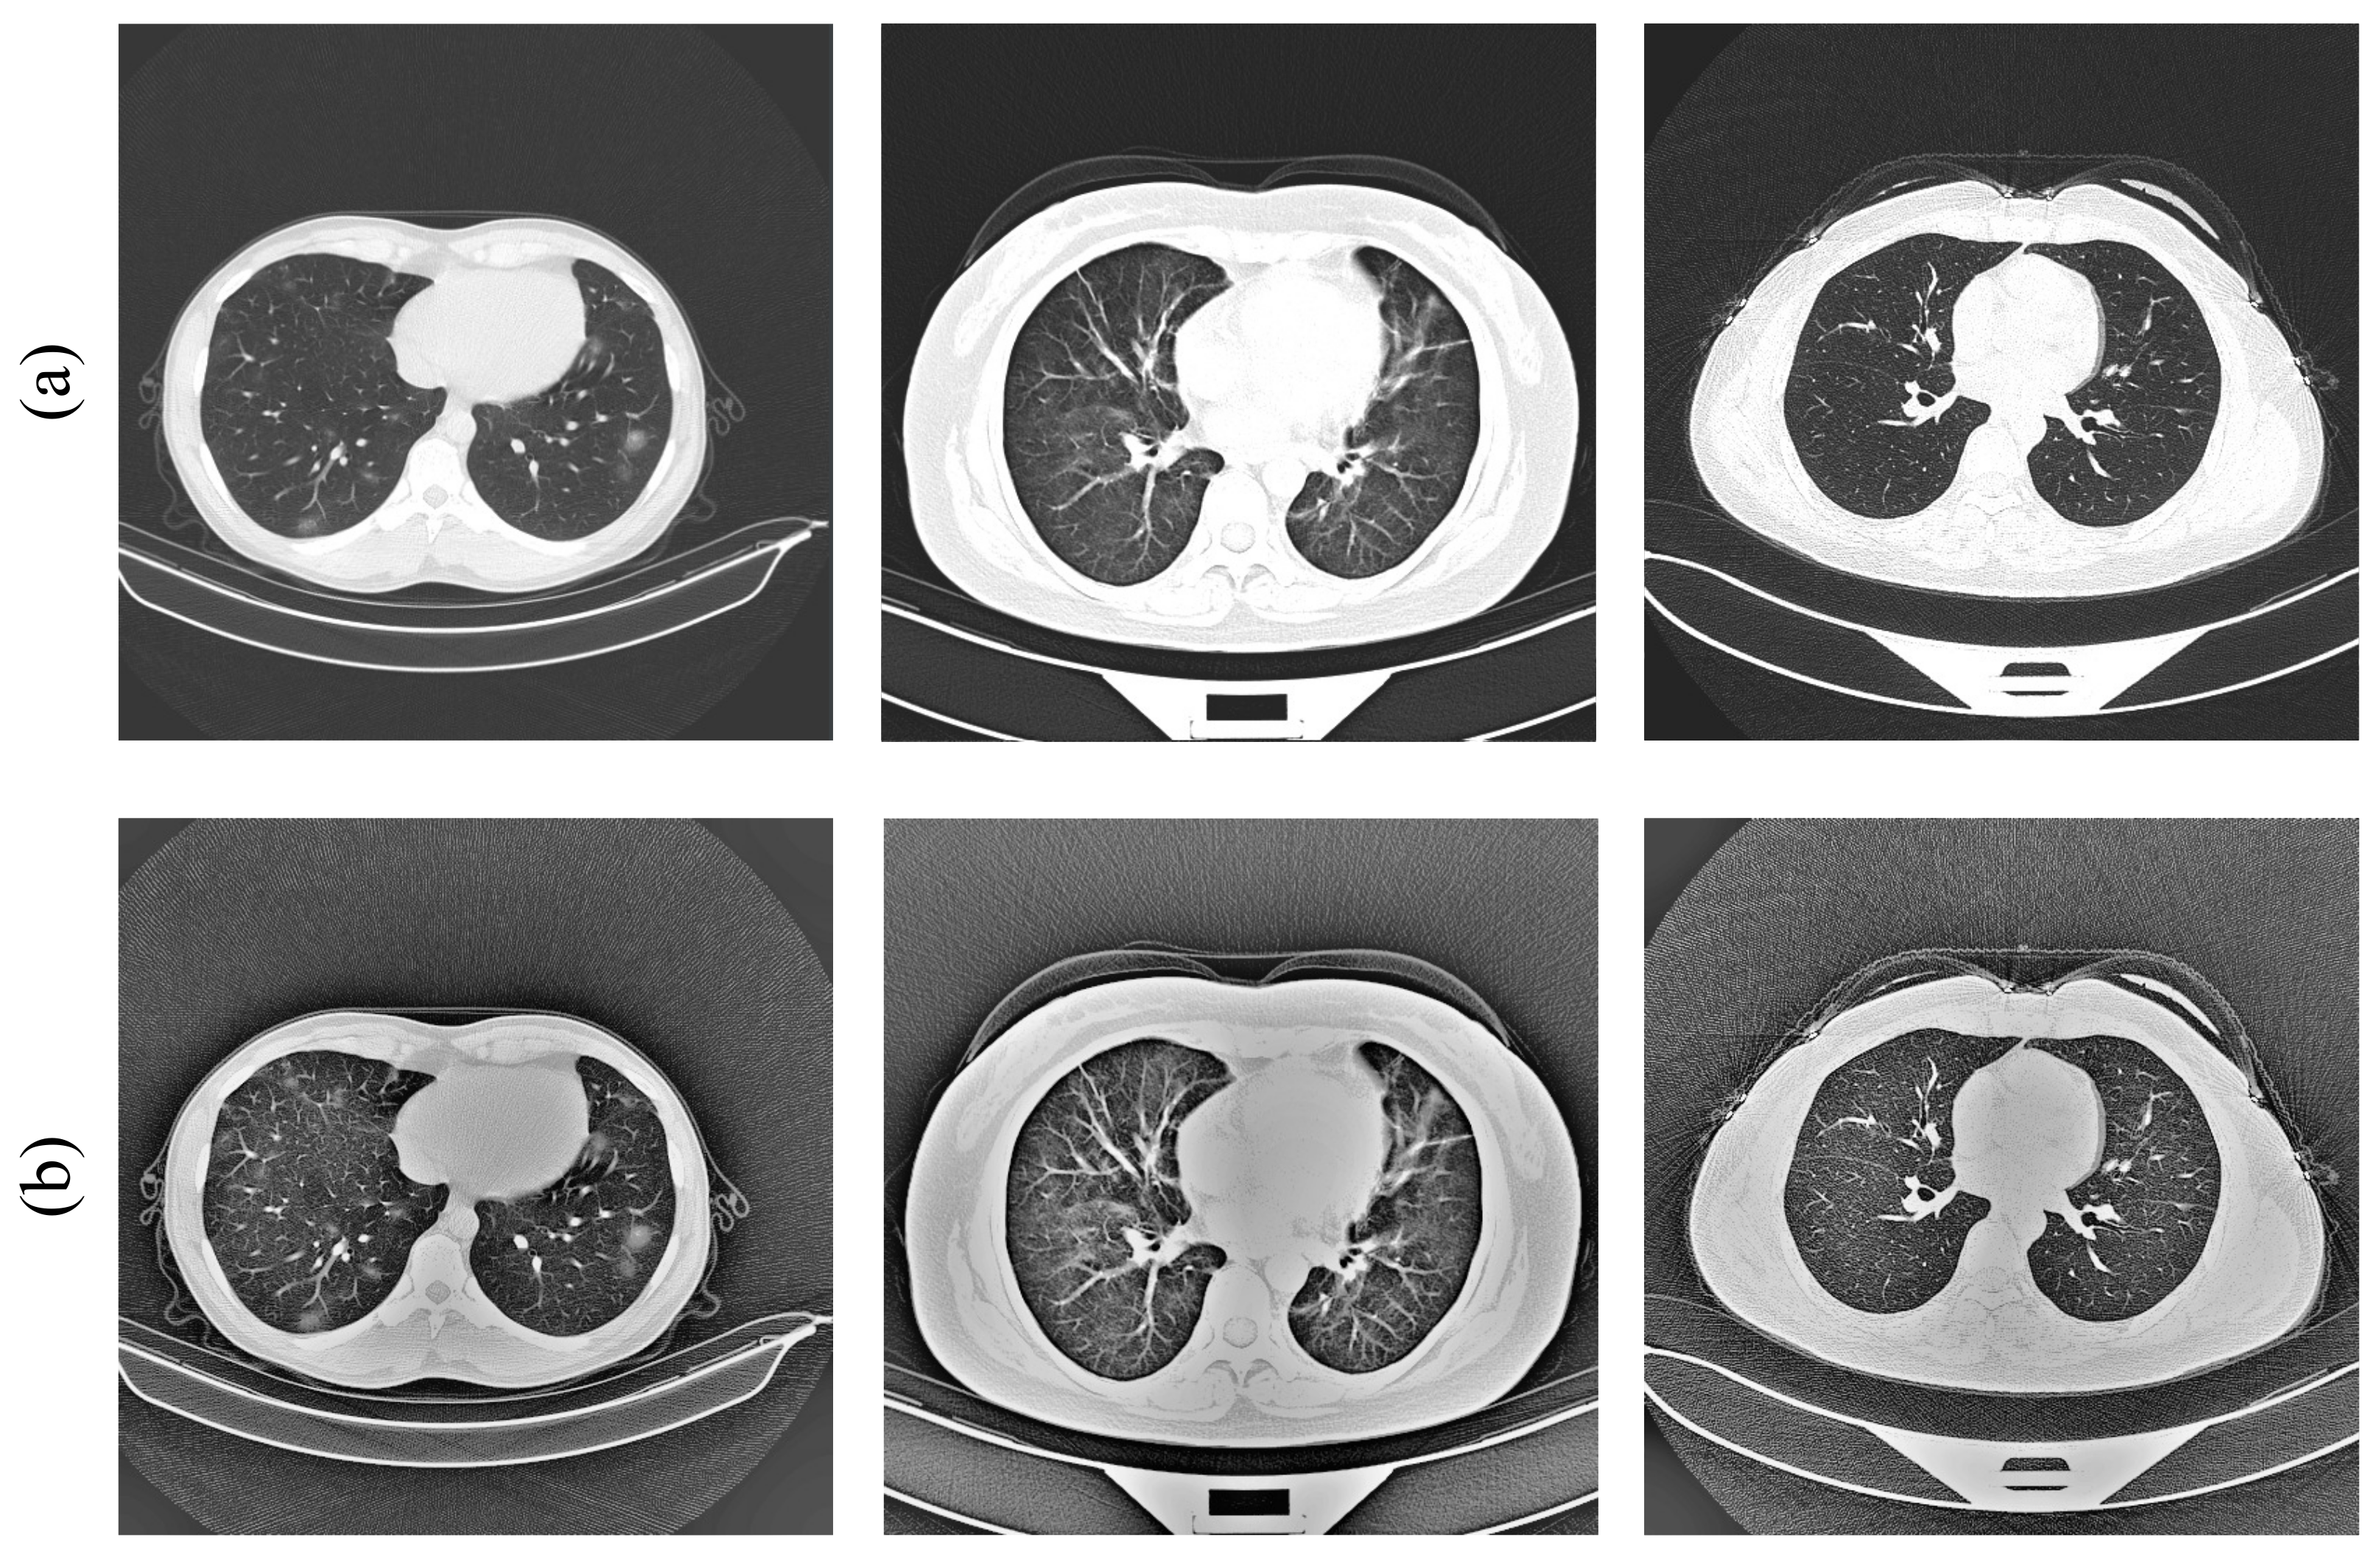

The most commonly used method for detecting SARS-CoV-2 is real-time reverse transcription polymerase chain reaction (RT-PCR). It is regarded as the gold standard for the diagnosis of SARS-CoV-2 due to its high sensitivity and high specificity [4,5], which is achieved by collecting samples from the upper respiratory tract (e.g., nasopharynx or oropharynx). However, this method is time-consuming and requires medical personnel with specialized skills, as well as a specific laboratory [6]. In addition, the RT-PCR method depends on the collected samples, and if the samples are not collected, transported, and stored appropriately, it could lead to false-negative results [7,8]. Another way to detect the disease is by computed tomography (CT) and X-ray, which is achieved by consolidation or ground glass opacity (GGO) in the lungs [9], as indicated by the red rectangular box in Figure 1. While both can be used for the diagnosis of COVID-19, chest CT images can show detailed information about the infected area. Some researchers found that the 98% sensitivity of chest CT is higher than the 71% sensitivity of RT-PCR by comparing CT images and RT-PCR tests at the initial patient visit [10]. This indicates that CT images of the lungs are more useful for the early diagnosis of patients.

Figure 1.

The lung CT image of a COVID-19 patient. (a–c) are ground glass images. The original image comes from the COVIDx CT-2A dataset [11,12].